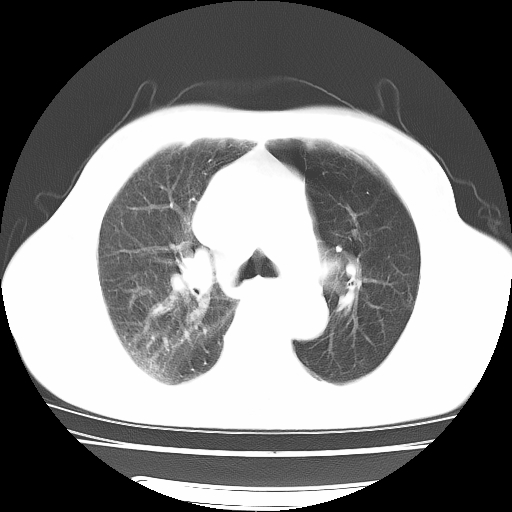

男,71岁,咳嗽,气喘10年,再发并咯血.胸片见气胸

考虑  左肺中心型肺癌伴阻塞性肺炎,肺不张,纵膈淋巴结肿大。慢支炎,肺气肿,左侧气胸肺压缩5%

左侧中央型肺癌伴纵膈淋巴结转移。

左肺中心型肺癌伴阻塞性肺炎,肺不张,纵膈淋巴结肿大

1)考虑左肺中心型肺癌伴阻塞性肺炎、左肺下叶肺不张、左侧肺气肿,纵膈淋巴结转移。2)左侧气胸(肺组织压缩约5%)。

左肺中心型肺癌伴阻塞性肺不张、肺气肿 。

1)考虑左肺中心型肺癌伴阻塞性肺炎、左肺下叶肺不张、左侧肺气肿,纵膈淋巴结转移。2)左侧气胸。